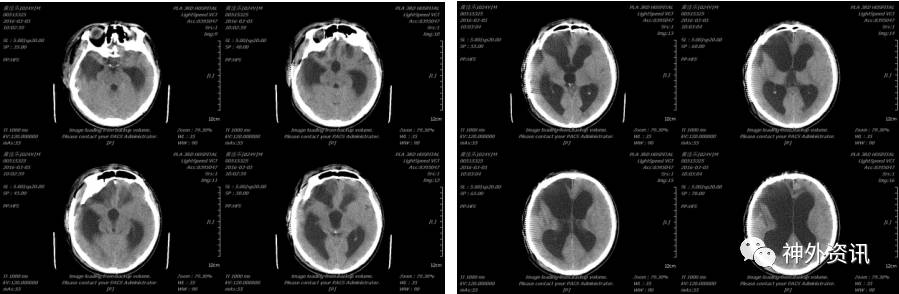

患者于2016-02-03能发简单“咿、啊”等音,但2016-02-26患者出现反应迟钝,大小便失禁等症状,复查头颅CT示(2016-02-26 14:25):

患者多次行腰穿症状缓解不明显,考虑脑积水,一方面病人各项情况逐渐好转,而且患者头皮状况较差,不适宜于立即行颅骨修补及分流,所以一直到伤后三个月行颅骨修补和分流手术。

于2016-03-04在全麻下行颅骨钛网修补术,2016-03-05复查头颅CT示(2016-03-05 10:02):

术后患者反应迟钝、大小便失禁等症状缓解不明显,于2016-03-15在全麻下行脑室-腹腔分流术,术后复查头颅(2016-03-16 11:59)示: